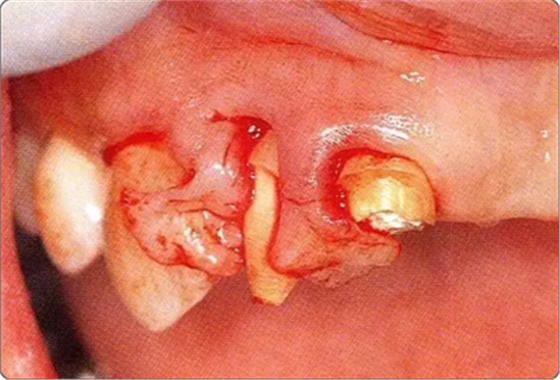

圖10-3 考慮到審美性,應(yīng)用牙齦乳頭保存術(shù)(Papilla preservation technique),進(jìn)行了自體骨移植。